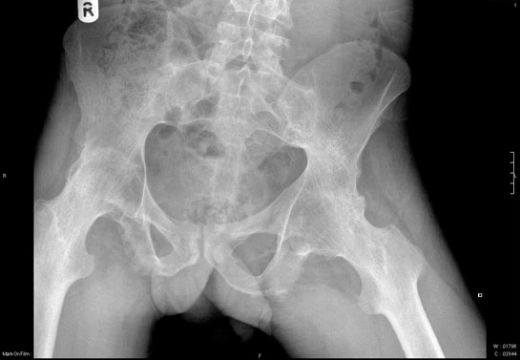

Osteoartrit, eklem kıkırdağının aşınması sonucu meydana gelen kronik bir hastalıktır. Bu hastalık, eklem yüzeyinin bozulmasına ve kemiklerin birbirine sürtünmesine yol açar. Zamanla, vücut bu durumu dengelemek için kemik çıkıntıları oluşturur. Bu osteofitler, eklem hareketliliğini kısıtlayabilir ve ağrıya neden olabilir.

Eklem bölgelerinde meydana gelen yaralanmalar ve travmalar, kemik dokusunun hasar görmesine ve onarım sürecinde osteofitlerin oluşmasına yol açabilir. Özellikle sporcularda sıkça görülen bu durum, eklemdeki kıkırdağın zedelenmesiyle ilişkili olarak ortaya çıkar.